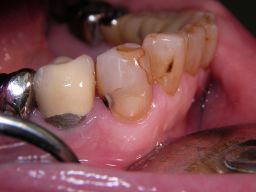

![]() | Der Eckzahn (Zahn 43) in der Mitte des Bildes zeigt an mehreren Stellen am Füllungsrand schwarze Karies, wie man hier aus verschiedenen Perspektiven sieht. Der Zahn rechts daneben auf dem Foto (Zahn 42) zeigt eine schwarze Randverfärbung einer älteren Kunststofffüllung. |

![]() | |||||||||||||||||||||||||||||||||||||||||||||||||||||||||||||||||||||||